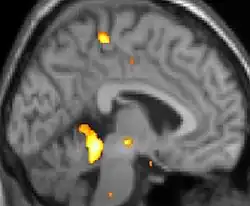

Viele bildgebende Verfahren der Medizin, wie die Magnetresonanztomographie, Ultraschall oder Röntgentomographie, oder der Physik, wie die Thermographie, erzeugen Bilder, die keine Farbinformation enthalten. Für solche Bilder erzielt man eine farbkodierte Darstellung, indem die einzelnen Graustufen durch unterschiedliche Farben repräsentiert werden, um kleine Nuancen im Bild deutlich zu erkennen.[2] Bilder zur Darstellung von Temperaturunterschieden werden Heatmap genannt. Eine unverzerrte und universell-lesbare Darstellung von Daten wird mit wissenschaftlichen Farbskalen erreicht.[2]

Beispielsweise können in einer Röntgentomographie verschiedene Gewebetypen in verschiedenen Farben dargestellt werden. Grundlage dafür ist eine hohe Farbauflösung des verwendeten Scanners.